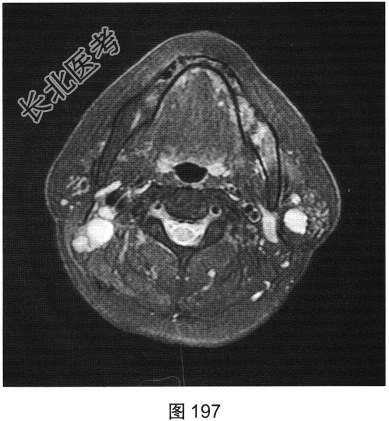

- 简答题2、患者行颈部平扫MRI检查,如图196~图199所示。请问患者MRI检查的阳性影像学表现有哪些?